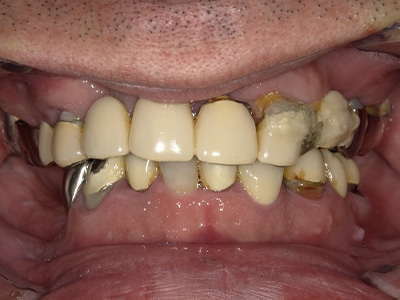

見た目も噛み心地も妥協しない

「補綴主導型インプラント」

一切妥協しないインプラント

最終的な被せ物(補綴)の理想的な形・位置から逆算し、インプラントを噛み心地と見た目に最適な位置に設計・埋入します。

技工士と院長が共同で設計し、その中心に正確にインプラントを配置。自然な見た目と快適な噛み心地の両立が可能になります。